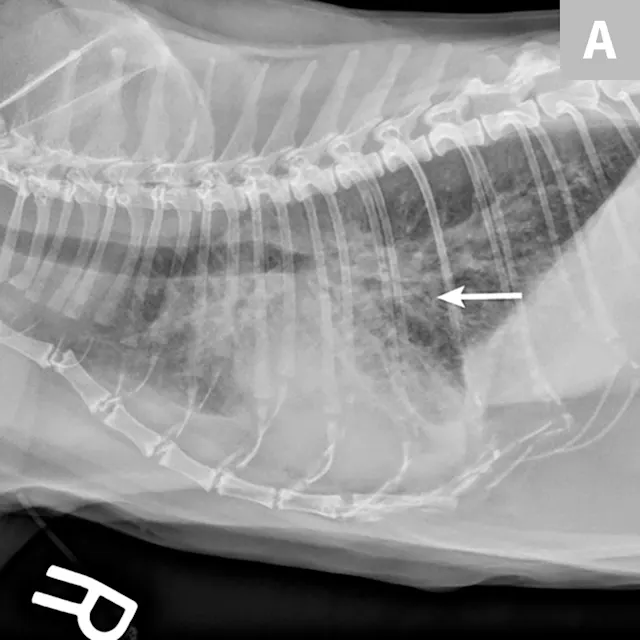

Lipid pneumonia may be appreciated in cats secondary to exogenous inhalation of oil (eg, mineral oil) or endogenous generation secondary to obstructive pulmonary disease (eg, bronchial disease, neoplasia). Radiographic features vary widely and can include diffuse interstitial, bronchointerstitial, or nodular patterns (Figure 7). Pleural effusion may be noted. These findings may represent the underlying obstructive disease.36,37

FIGURE 7

Endogenous lipid pneumonia confirmed on lung biopsy (orange arrow, biopsy site). The origin of the lipid pneumonia could not be identified in this case. Note the patchy unstructured interstitial opacities (red arrows).